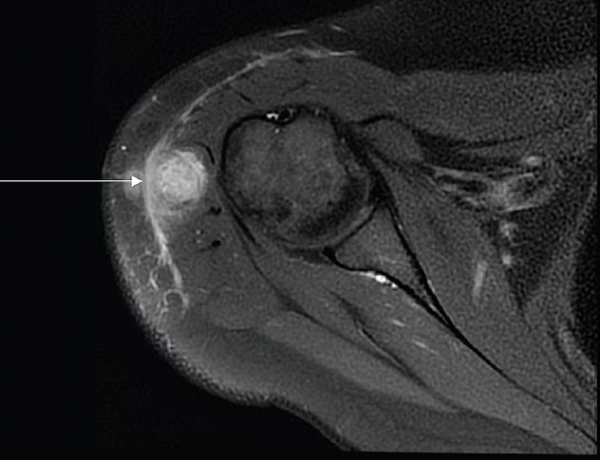

Zdrava 30-letna bolnica je pomotoma prejela cepivo proti tuberkulozi, kar je povzročilo okužbo celega telesa in s tekočino napolnjen absces v deltoidni mišici, označen s puščico.

Zdravniki so oteklino sprva pripisali vnetemu kožnemu tkivu, vendar so preiskave kasneje potrdile bakterije, ki povzročajo tuberkulozo v njenem telesu.